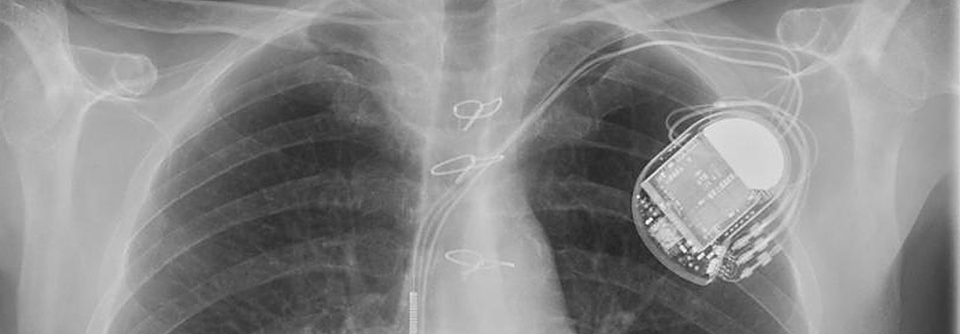

Diese Thoraxaufnahme zeigt das implantierte LVAD einer 65-jährigen Patientin mit Herzinsuffizienz. Diese Thoraxaufnahme zeigt das implantierte LVAD einer 65-jährigen Patientin mit Herzinsuffizienz. © Science Photo Library/Zephyr

In erster Linie kommen zur Kammerunterstützung linksventrikuläre Systeme (left ventricular assist device, LVAD) zum Einsatz. Etwa 900 dieser Geräte werden pro Jahr in Deutschland implantiert und halten bis zu zehn Jahre, berichtete PD Dr. Gloria Färber von der Klinik für Herz- und Thoraxchirurgie am Universitätsklinikum Jena. LVAD bringen einen erheblichen Gewinn an Lebenszeit gegenüber einer konservativen Therapie. Hinsichtlich des Zwei-Jahres-Überlebens stehen sie den Erwartungen nach einer Transplantation kaum nach (70 % bzw. ca. 75 %).